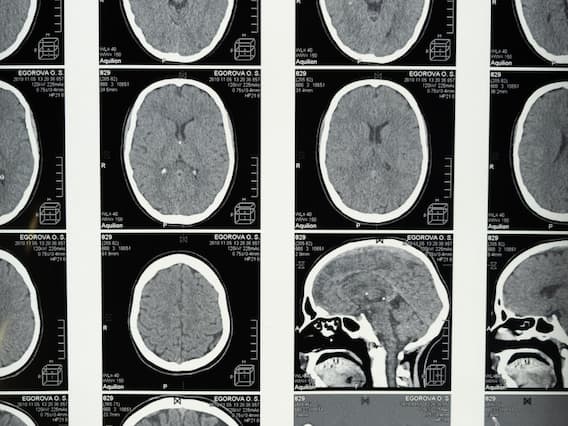

How to save a stroke victim from dying: ఈ మధ్య కాలంలో బ్రెయిన్ స్ట్రోక్ మరణాలు ఎక్కువగా సంభవిస్తున్నాయి. ఉన్నట్లుండి మెదడుకు రక్తం సరఫరా నిలిచిపోతే బ్రెయిన్ స్ట్రోక్ వచ్చే ప్రమాదం ఎక్కువగా ఉంటుంది. ఫలితంగా అది పక్షవాతానికి కూడా దారి తీసే ప్రమాదం లేకపోలేదు. కొన్నిసార్లు మరణం కూడా సంభవిస్తుంది. అయితే ఈ బ్రెయిన్ స్ట్రోక్ రావడానికి కారణాలు ఏంటి. బ్రెయిన్ స్ట్రోక్ లలో రకాలు, ఈ వ్యాధి లక్షణాలు, నివారణకు తీసుకోవల్సిన జాగ్రత్తలేంటో తెలుసుకుందాం.